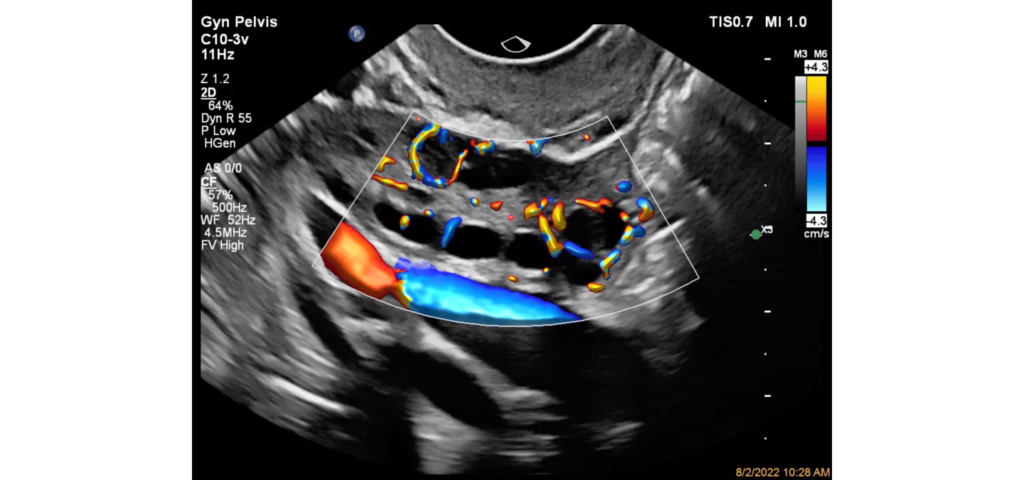

Philips EPIQ Elite ultrasound features an exceptional level of clinical performance, workflow, and advanced intelligence to meet the challenges of today’s most demanding practices. The EPIQ Elite platform brings ultimate solutions to ultrasound, with clinically tailored tools designed to elevate diagnostic confidence to new levels.